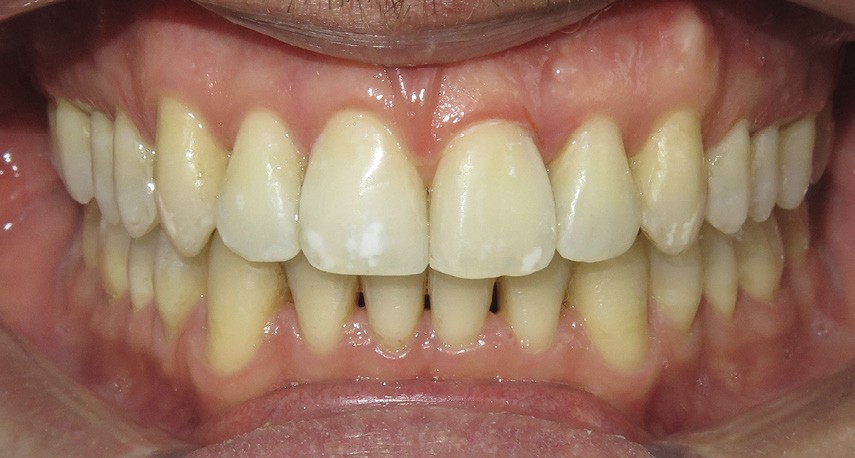

Diagnostic (fig. 1a-i)

Le patient consulte initialement pour des défauts d’alignement. L’examen clinique confirme l’existence d’un encombrement antérieur bimaxillaire, mais révèle aussi la présence d’une Classe II dentaire sévère, d’une exoclusion de la 27 et de troubles parodontaux (peu ou absence de papilles inter-dentaires). Sur le plan squelettique, le patient est relativement équilibré avec un profil harmonieux.